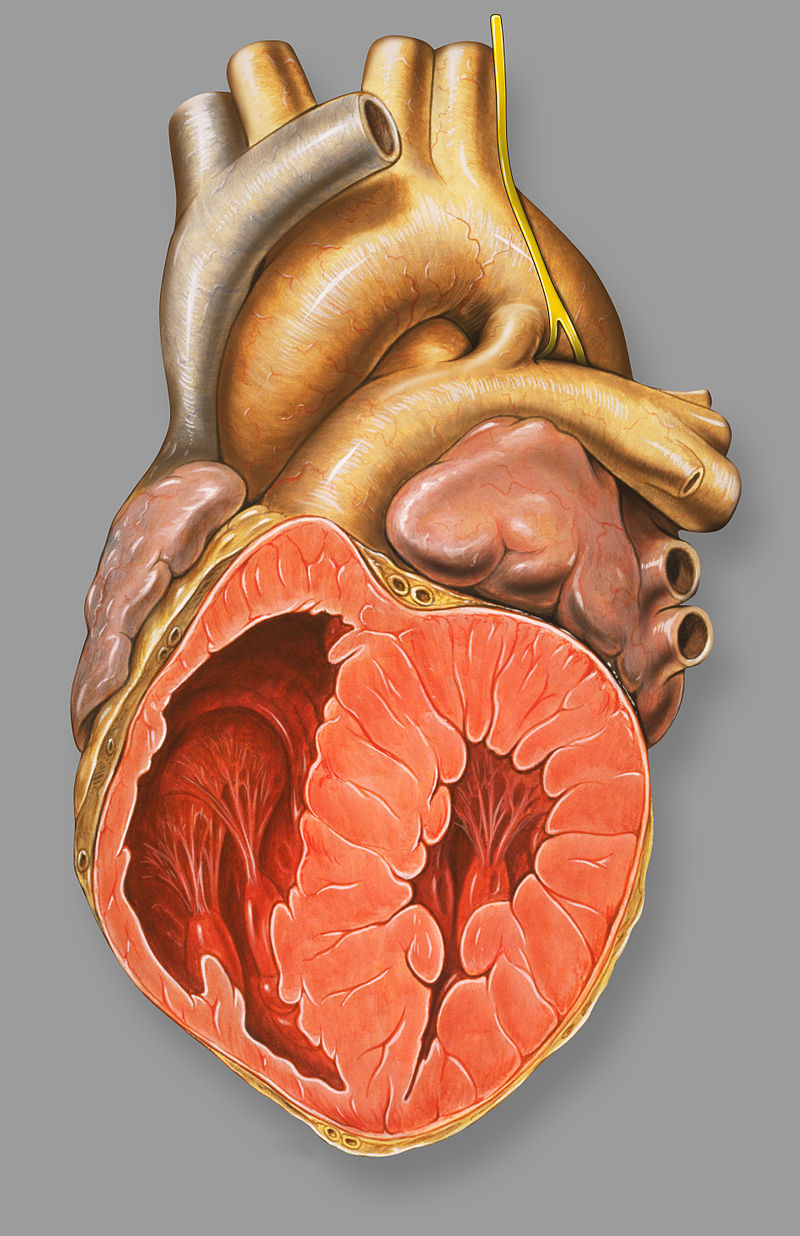

Congenital Heart Defects

Congenital heart defects occur throughout embryogenesis (usually weeks 3 through 8).

Congenital heart defects are observed in 1% of live births.

Most congenital heart defects are incidental and not clinically significant.

Congenital heart defects frequently cause shunting between the right (pulmonary) and left (systemic) circulations.